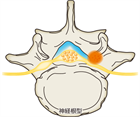

1. 馬尾型もしくは混合型の腰部脊柱管狭窄(LSS)による間欠跛行患者にはリマプロスト投与を推奨する(推奨度2)